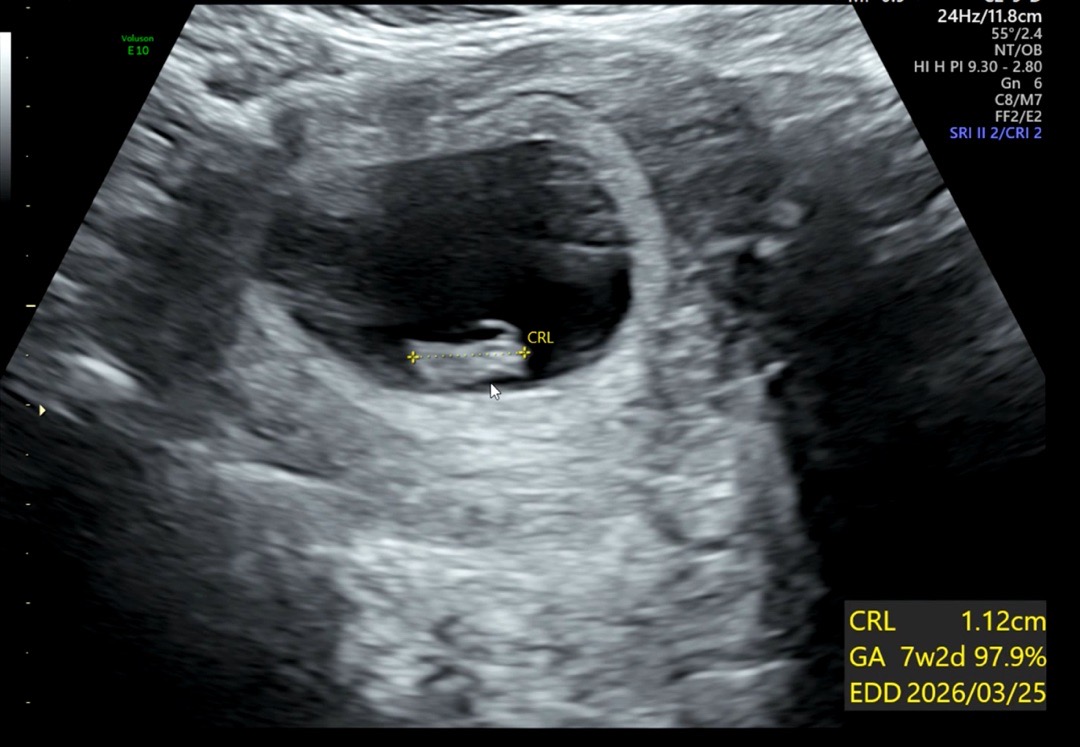

7주4일 아기가 1cm래요!

지난주에 갈땐 아기가 0.5cm였는데 일주일새 두배나 컸네요ㅠㅠ 감격 ,, 심장도 빠르게 잘뛰고 있다고 해서 안심됐어요. 원래 정기검진은 일주일 남았는데 잘크고 있나 너무너무 궁금해서 현장대기 2시반 넘게 하고 보고왔어요👶🏻 이번주 정기검진땐 하리보 볼수 있겠죠??🩷